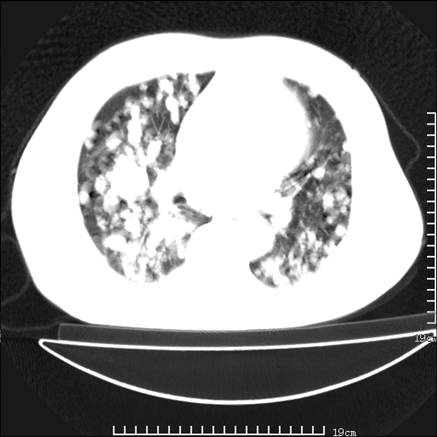

张男,75岁,干咳半年余,小便不利二年,b超检查前列腺增大,未见明显肿块;前列腺癌血生化检查多项指标明显增高。

双肺内多发转移瘤,纵膈淋巴结转移。来源前列腺?建议盆腔mri进一步检查。

双肺转移满了。

两肺广泛转移瘤。